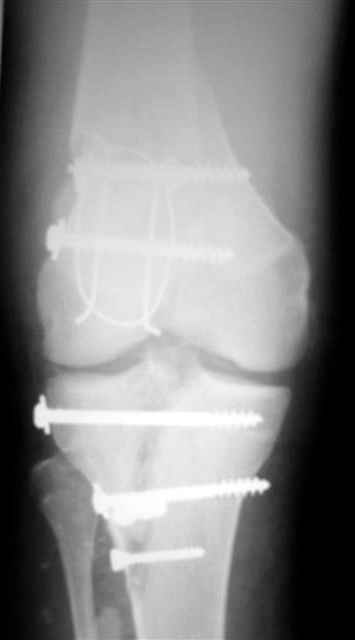

Спасибо за комментарии. Травма тяжелая с проблематичным прогнозом для функции коленного сустава( изначально травма разгибательного аппарата с последующим частичным некрозом собственной связки надколенника и о обнажением рефиксированного фрагмента бугристости большеберцовой кости, дефектом центрального отдела суставной поверхности большеберцовой кости и медиального отдела капсулы сустава).